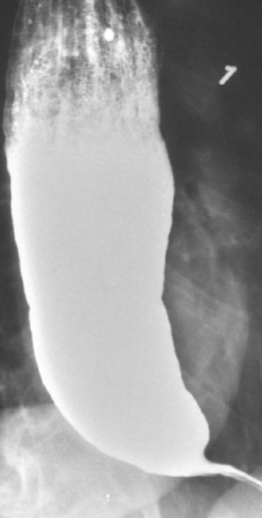

Esophageal Diverticula

Most are acquired Pseudodiverticula (herniations of mucosa only) associated with dysmotility

Increased intraluminal pressures & wall stress from the dysmotility syndromes may cause pulsion type Diverticula

Right above the LES (Epinephric Diverticulum)

Impaired relaxation & spasm of Cricopharyngeal muscle after swallowing → Pharyngoesophageal Diverticulum (Zenker)

Zenker → Dysphagia & sense of a lump in the throat; food trapping leads to regurgitation of food, chronic cough; Halitosis; Infection

Zenker Diverticulum

Epinephric Diverticulum